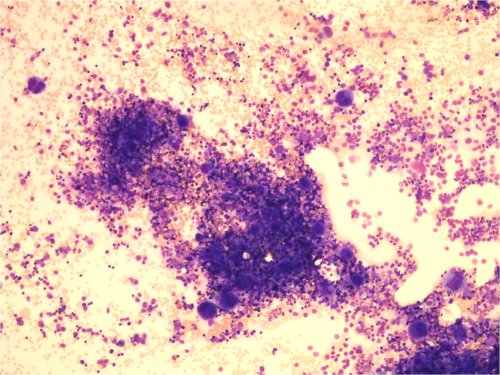

Kuva 2. Vaikea aplastinen anemia. Näkyvissä 1) rasvaa, 2) stroomasoluja ja 3) lymfosyyttejä.

Kuva 3. Vaikea aplastinen anemia. Näkyvissä rasvaa, 1) stroomasoluja ja 2) lymfosyyttejä.

Kuva 4. Vaikea aplastinen anemia. Näkyvissä 1) plasmasoluja ja 2) kudosbasofiili (tissue mast cell).